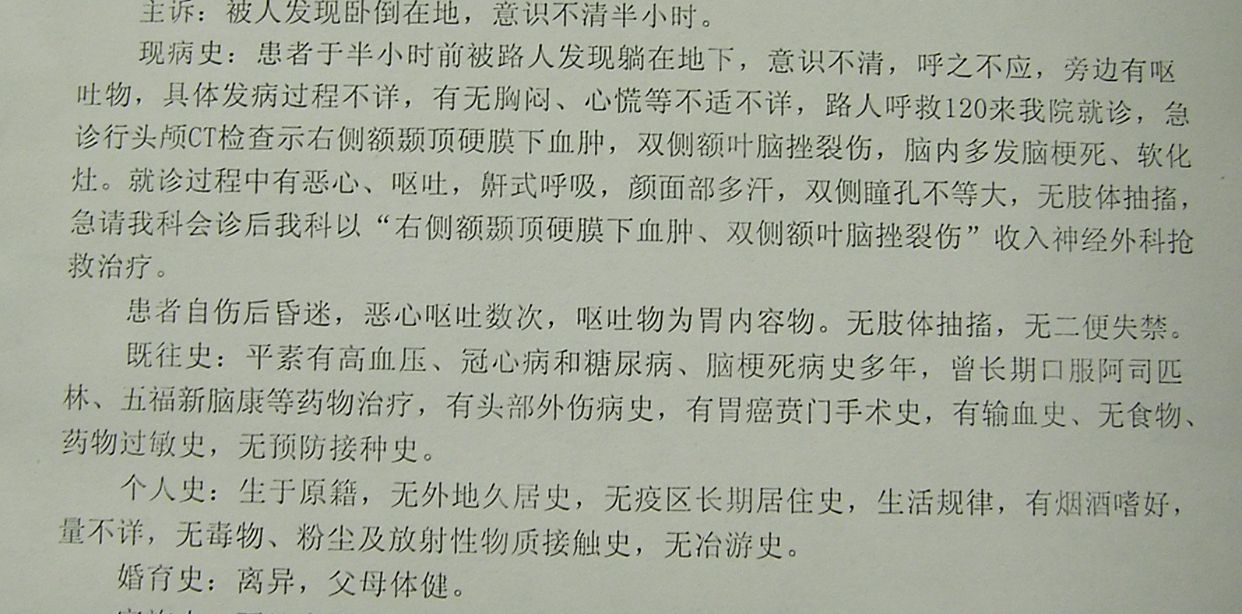

例2,男,63岁,被发现卧倒在地意识不清半小时入院。

CT示右额颞顶大量硬膜下血肿,右额颞叶脑挫裂伤,中线明显移位。急症全麻下开颅,血肿清除去骨瓣减压术,及气管切开术。

术后CT复查示,血肿清除彻底,中线居中,额颞叶水肿期。

术后8天,患者出现呼吸困难,氧饱和度下降,胸部CT示左侧肺野消失,考虑胃膈疝并肺不张肺感染。调整体位,拍背吸痰,应用呼吸机辅助呼吸等治疗。

术后3周CT复查,脑水肿消退,中线居中。

胸部CT复查,肺不张恢复,肺部阴影消退。患者恢复意识,遵嘱动作,呼吸良好,体温血象正常,出院康复。